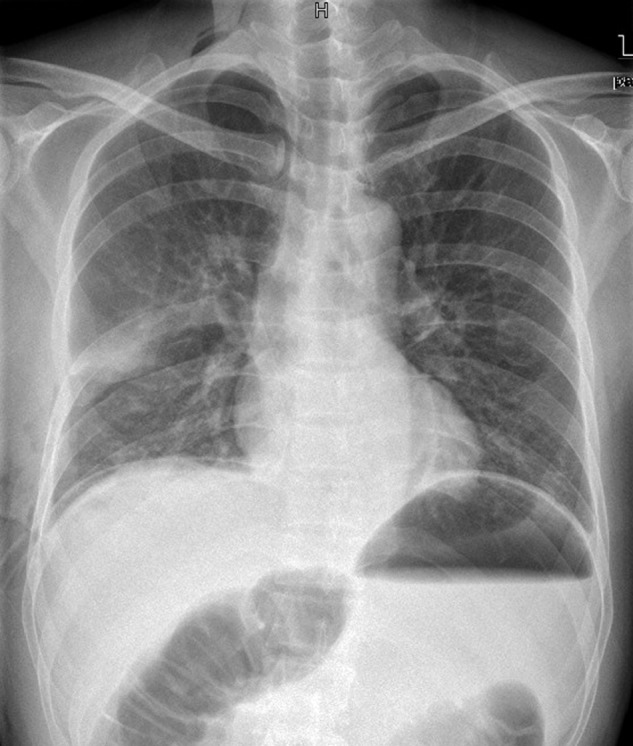

A 47‐year‐old man presented with a two‐month history of constant cough, chest distress, and slight dysphagia. Physical examination revealed that breathing sounds were markedly decreased throughout the right thorax and the sound of the heart had moved to the left side. Chest radiography showed a high‐density shadow in the lower two‐thirds of the right thorax (Fig 1a). Enhanced computed tomography (CT) of the chest confirmed a huge mass with fat tissue density in the posterior mediastinum, which extended to the bilateral thorax and compressed the heart, aorta, and bilateral lung (Fig 1b). Upper gastrointestinal contrast showed an obvious dislocated esophagus, resulting from compression of the mass. Bronchoscopy revealed that the right middle and lower lobe bronchi were distorted, and the lumen had become severely narrowed. Cranial and abdominal CT scans and a bone scan excluded the potential metastasis of the tumor. Blood biochemistry and serum cancer markers were all normal.

Figure 1.

(a) Chest radiography showed a high‐density shadow in the lower two‐thirds of the right thorax. (b) Enhanced computed tomography of the chest confirmed a huge tumor with fat tissue density in the posterior mediastinum. The tumor extended to the bilateral thorax and compressed the heart, aorta, and bilateral lung.